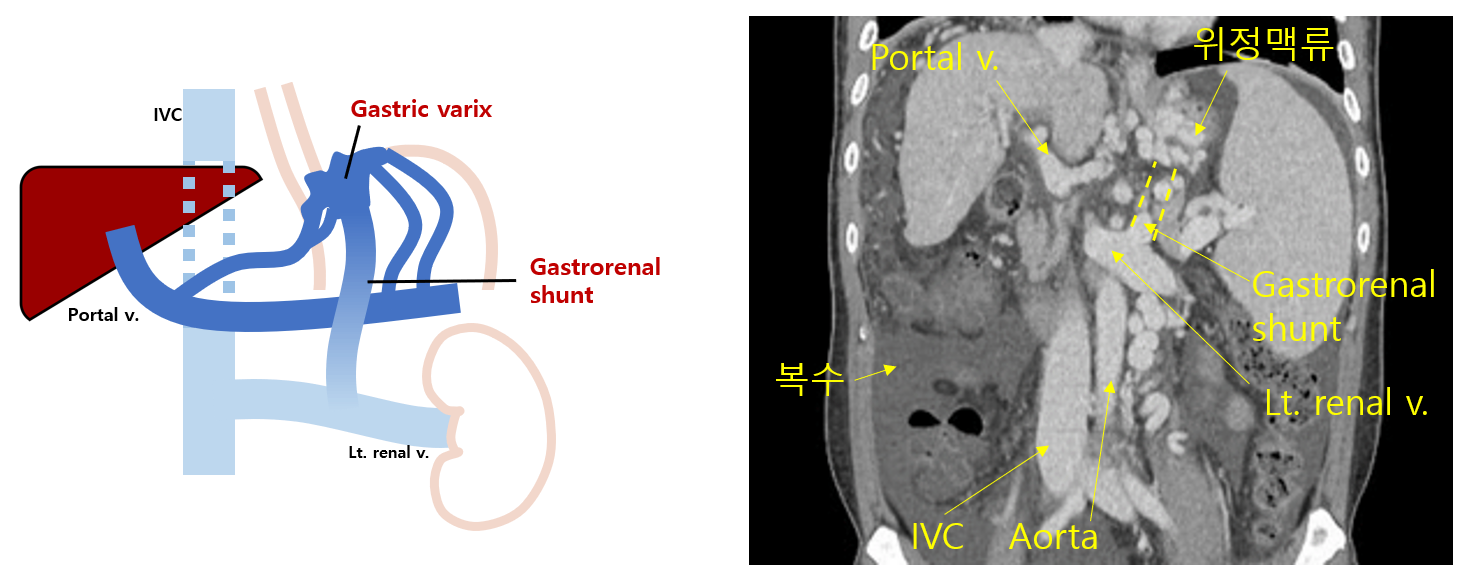

Img | CT: Engorged gastric varices, gastrorenal shunt, ascites, splenomegaly |

• UGI bleeding의 진단적 검사인 EGD상 위정맥류가 관찰되고, CT에서도 portal HTN으로 인한 위정맥류가 두드러진 모습이 보이며, 위의 fundus까지 침범한 것을 볼 수 있다. 또한 splenomegaly도 보이며, 이로 인해 thrombocytopenia가 있음을 추론할 수 있다.

• CT상 위정맥류와 Lt. renal v. 사이의 샛길인 gastrorenal shunt가 있음이 추정된다. 심한 portal HTN으로 인해 발생할 수 있다.

• 위정맥류가 식도정맥류에서 이어져 fundus까지 이어졌을 경우(GOV2), 재출혈 예방을 위해 내시경정맥류페쇄술(EVO), BRTO, TIPS를 시행할 수 있다. 본 증례의 경우 간성 뇌증이 의심되므로 TIPS의 금기증에 해당하고, 따라서 EVO 또는 BRTO를 시행해야 한다. BRTO는 gastrorenal shunt가 있을 경우 이 shunt를 통해 위정맥류에 접근해 정맥류를 폐쇄하는 시술이다.